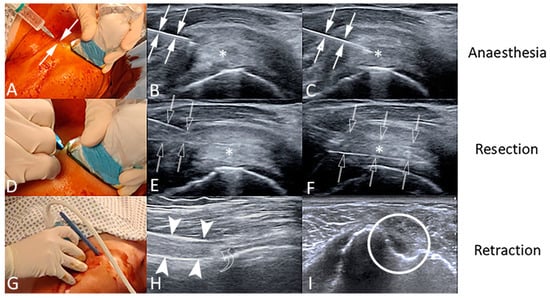

2.2. Tenotomy